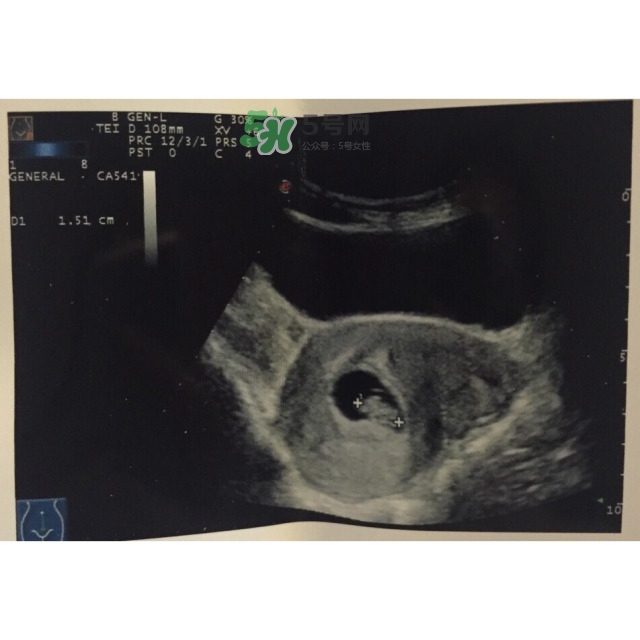

* 2016年10月5日孕8w+3

第一次做B超,胎兒太小,只見孕囊,未見卵黃囊和胚芽

* 2016年10月15日孕9W+6

第二次做B超,已見卵黃囊和胚芽